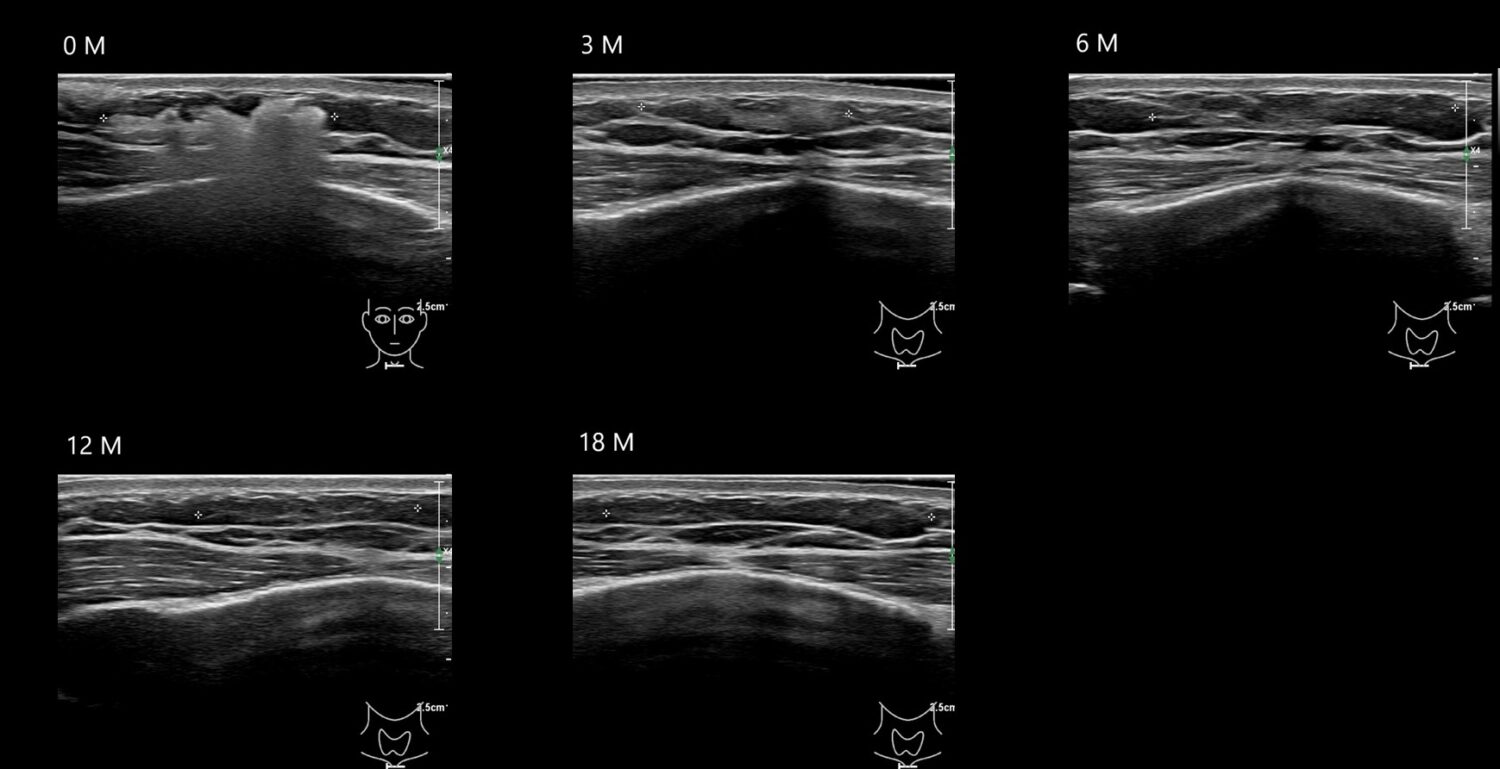

Filler library

O CAHA 21 E

O CAHA11 E

O CAHA12 E

O CAHA13 E

O CAHA16 E

O CAHA20 E

o caha4 E

O CAHA5 E

o caha6 E

O CAHA7 E